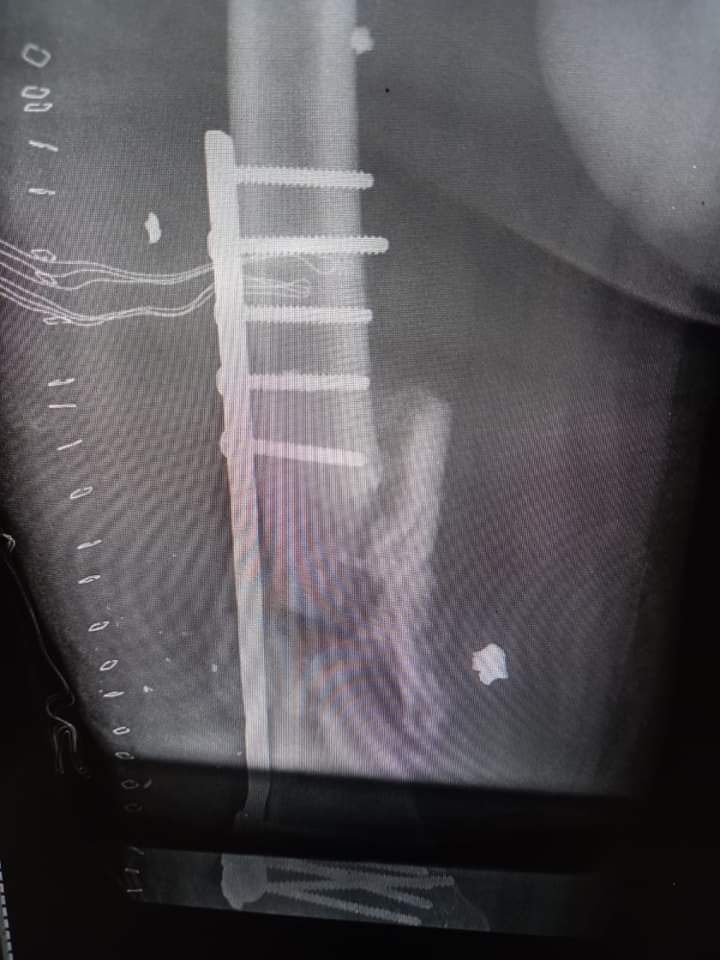

تنفيذاً لتوجيهات جلالة الملك عبد الله الثاني القائد الأعلى للقوات المسلحة، ومتابعة من القوات المسلحة الأردنية الجيش العربي، بدعم قطاع غزة طبياً وصحياً والوقوف إلى جانبهم ومساندتهم، واصلت طواقم المستشفى الميداني الأردني غزة/78 تقديم خدماتها الطبية والعلاجية والإنسانية للأهل في قطاع غزة.

وقال قائد قوة المستشفى: "إن المستشفى يمثل لفتة إنسانية ملكية وامتداداَ لمسيرة الخير والعطاء الأردنية منذ انطلاقه في عام 2009 ولغاية هذه اللحظة"، مشيراً إلى أن الطواقم الطبية تسعى دائماً إلى تقديم أفضل الخدمات الطبية والعلاجية للأشقاء في قطاع غزة.

واوضح قائد القوة أن اجمالي عدد مراجعي المستشفى الميداني الأردني غزة/78 منذ بدء عمله حتى اليوم تجاوز (18) ألف مراجعاً، وبلغت العمليات الجراحية التي تم اجراؤها (41) عملية جراحية كبرى و(16) عملية جراحية صغرى.